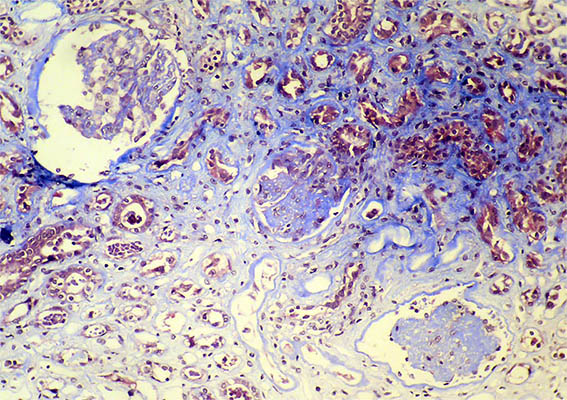

Figure 1. Masson's trichrome stain, X100.